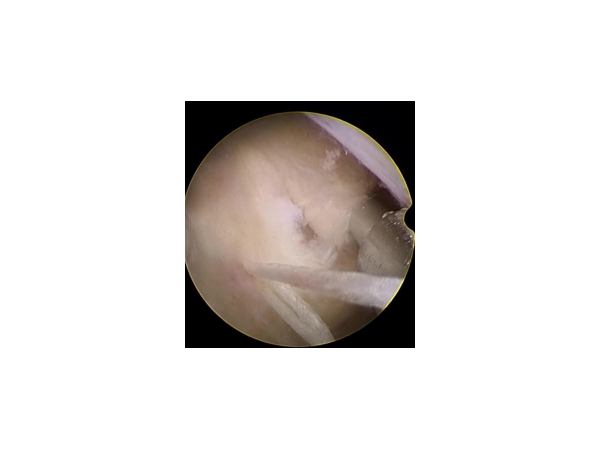

產(chǎn)品說明:一次性纖維環(huán)縫合器技術(shù)的意義在于:1、纖維環(huán)縫合術(shù)是把造成椎間盤突出癥狀的病因,即損壞的纖維環(huán)修復(fù)上。椎間盤突出的根本原